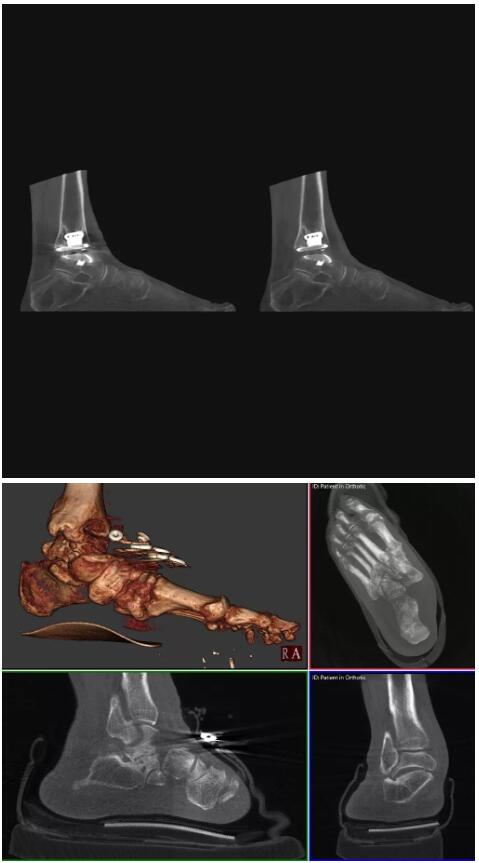

比如上面這款專用于足部和踝部掃查的CT成像系統(tǒng),患者在進行CT掃查時只需要站在上面即可,雙腳站或者單腳站都可以,當然,如果患者不是那么方便站著做完CT掃查,也可坐在上面。

這款CT掃查系統(tǒng)自帶屏蔽裝置,它的體積非常小,僅需要極小的空間即可,并不像常規(guī)CT那樣需要一間單獨的檢查室。此外,這種CT掃查的速度非???,僅需30秒左右可以完成檢查,輻射劑量相對常規(guī)的CT要少許多,尤其適合醫(yī)院的骨科使用。

而患者站著做足部或者踝部做CT檢查還有個好處是,可以檢查患者在負重的情況下,骨關(guān)節(jié)的真實情況,而躺著做CT掃查時未必能看出來。負重CT掃查特別是對于受傷的運動員或者舞蹈員來說意義更大,能夠更準確地評估傷情,幫助他們盡早復原。

以下是這些“特立獨行”的CT所拍出來的圖像: